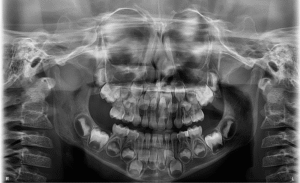

Na imagem panorâmica apresentada, observam-se dois dentes supranumerários localizados na região anterior da maxila, sobrepostos aos germes dos dentes 11 e 21 (incisivos centrais superiores).

• Localizar exatamente os dentes supranumerários;

• Avaliar sua relação com os germes permanentes;

• Evitar complicações cirúrgicas e garantir a preservação das estruturas anatômicas vizinhas.